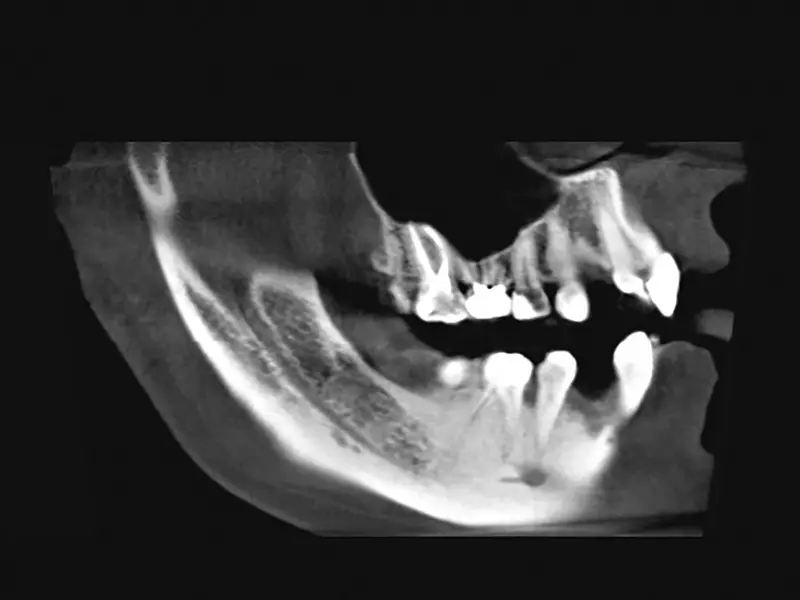

Pacjent, lat 19, leczony ortodontycznie. Ze względu na brak zawiązków zębów 12. i 22. zaplanowano leczenie implantologiczne. Biorąc pod uwagę ukształtowanie wyrostka zębodołowego w tych okolicach oraz możliwość powstania fenestracji wierzchołkowej w czasie wprowadzania implantów, przewidywano konieczność zastosowania materiału kostnego. Pacjent „dysponował” własnym materiałem kostnym w postaci dwóch zatrzymanych trzecich zębów trzonowych. Uznano, że ilość materiału pochodząca z jednego trzonowca będzie wystarczająca do zaopatrzenia obu miejsc implantacji.

Usunięto ząb 48., a następnie poddano go działaniu 3-procentowego roztworu wody utlenionej przez 3 minuty. Oczyszczono z włókien ozębnej, a następnie umieszczono na sucho w pojemniku, który był przechowywany w temperaturze 8°C do czasu zabiegu implantacji.

W dniu zabiegu ząb skruszono tak, aby uzyskać drobiny wielkości 800–1000 µm, które są optymalne dla procesu regeneracji kości. Po rozdrobnieniu otrzymano 1,5 cm³ materiału kostnego.

Autogenny materiał kostny pochodzenia zębowego umieszczono w ubytku tak, aby pokrył odsłoniętą powierzchnię implantu. Materiał po nasączeniu krwią był dostatecznie zwięzły i nie wymagał zastosowania dodatkowych membran. Po uwolnieniu okostnej pole operacyjne zostało zamknięte bez napięcia, umożliwiając gojenie podśluzówkowe implantu. Wargowy zarys wyrostka był bardziej wypukły niż przed augmentacją. Zaplanowano odsłonięcie implantów za 3 miesiące.